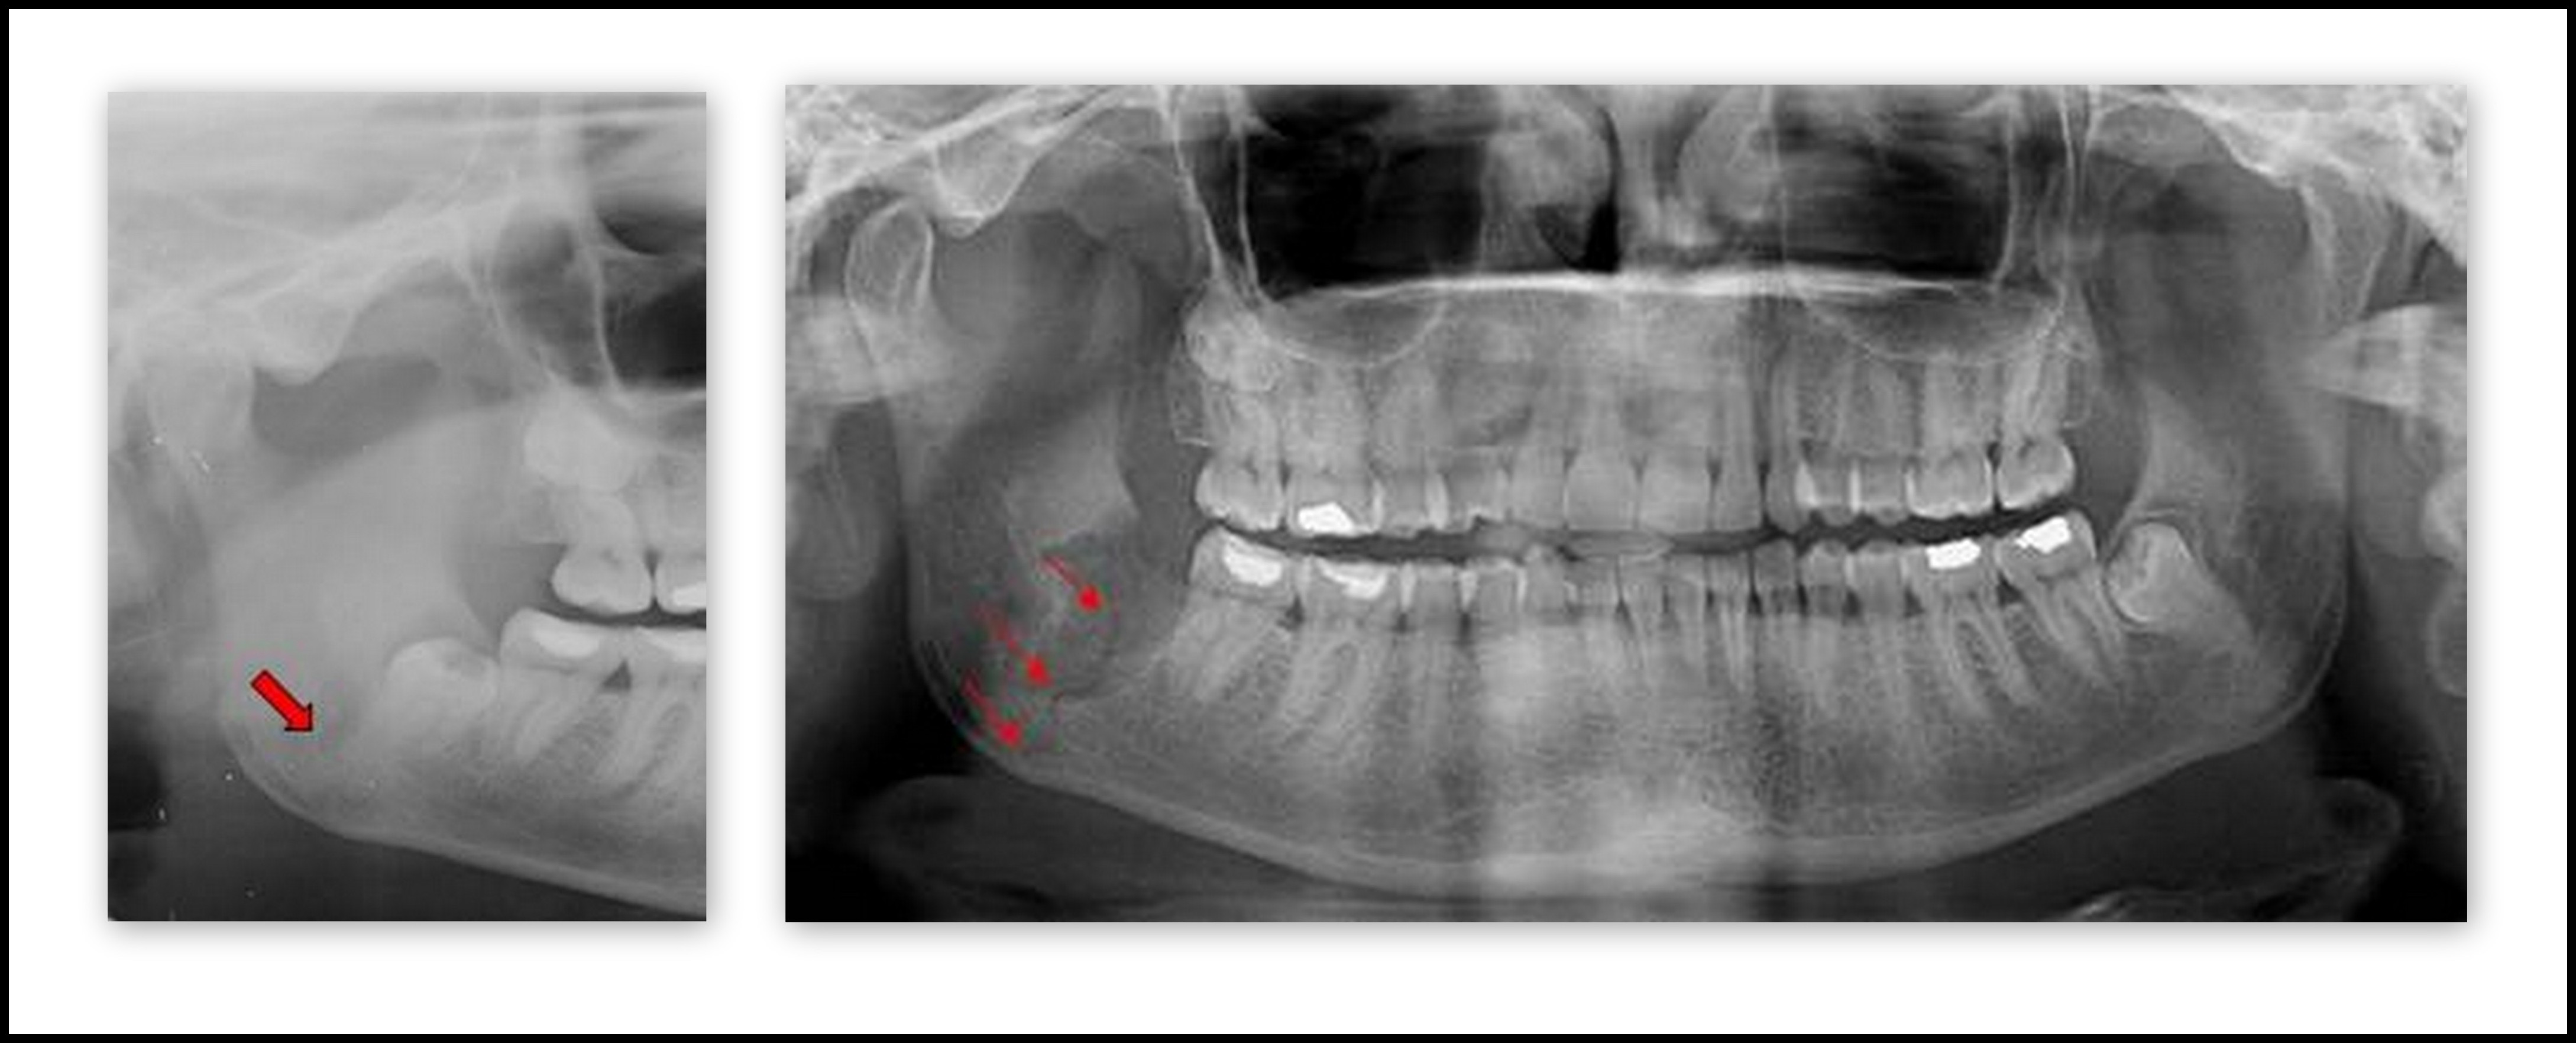

Similarly, certain tooth extraction cases are going to be more complicated than others. An example would be third lower molar extraction in a patient with a high risk of mandibular fracture.